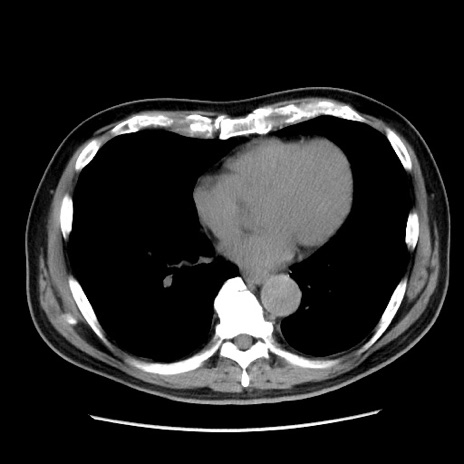

冠状断像